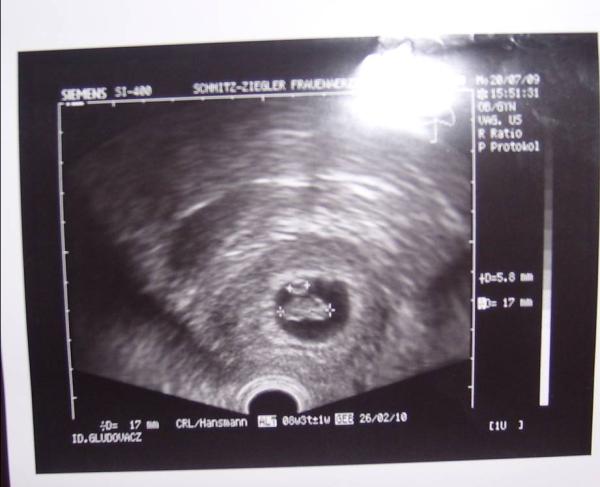

hallo ihr lieben.... ich hatte gestern meine erste VU beim arzt und bin total happy... dem baby geht es gut.... herzchen hat gebubbert... total süss.... laut rechnung wäre ich ja gestern erst bei 8+0 gewesen und die FÄ meinte, weil ich einen zyklus von 35 tagen hab kann es sein, dass ich noch nicht so weit wäre aber dann hat sie US gemacht und siehe da, das Baby ist sogar etwas grösser... Laut US war ich gestern bei 8+3... dann hätte ich laut us ET am 26.02.2010... sie möchte sich aber noch nicht festlegen.... wir kontrollieren das nochmal in 4 wochen... wenn ich darf bleib ich aber trotzdem bei euch im März-Forum, weil ihr alle sooo lieb seid... so, ich muss jetzt mal arbeiten... bin richtig happy... LG Daniela

ich denke schon das mein das herzchen sehen kann... drück dir auf jeden fall mal die daumen... ich hab erst am 25.8. VU da bin ich dann 12+ ?? aber wenn ich glück habe dann kann meine FÄ schon sehen was es wird... die ist da echt spitze... sieht das immer voll früh... bei einer freundin hat sie schon bei 11+4 gesehen das es ein mädchen wird... bin schon voll aufgeregt... das werden lange 4 wochen, aber zumindest weiss ich ja jetzt das alles in ordnung ist.. bild von meinem krümel hab ich natürlich auch bekommen...

Bild zu